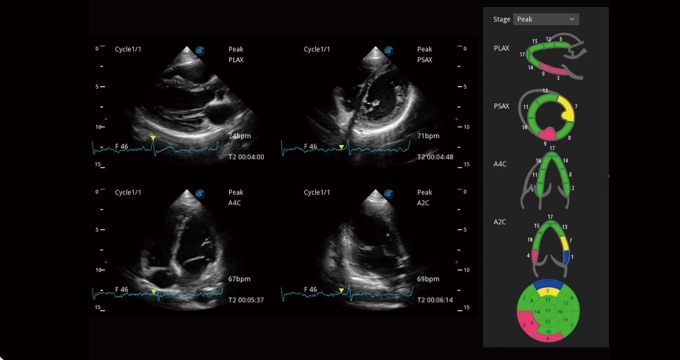

支持運(yùn)動(dòng)和藥物負(fù)荷協(xié)議、多心動(dòng)周期存儲(chǔ)選擇,為臨床觀察心肌負(fù)荷狀態(tài)下的室壁節(jié)段運(yùn)動(dòng)、評(píng)估心肌缺血狀態(tài)提供更多的解決方案。